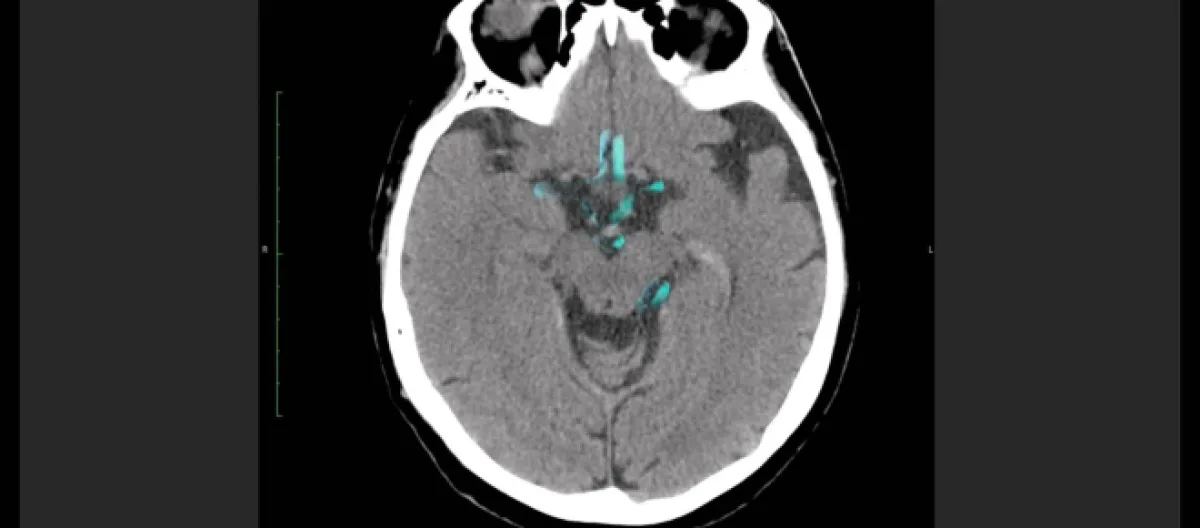

Pelos resultados de pesquisa obtidos e divulgados pela Revista Nature Neuroscience e utilizando-se da metodologia de pesquisa denominada "interação grupo por tempo", pode-se inferir que ocorria decrescimento em formação estrutural envolvendo a interação da região frontoparietal coligada a outras áreas do cérebro, como aquelas responsáveis pela atenção visual, dorsal, além de redes padrão e subcorticais.

Dessa forma, as ligações neuronais esperadas e necessárias à fase juvenil mostraram-se mais intensas (hiperconectividade), que do grupo neurotípicio no início do acompanhamento, mas decrescentes durante as próximas fases de acompanhamento (poda adaptativa).

O grupo neurotípico obteve aumento em intensidade na conectividade dessa interação-rede durante um longo-prazo em comparação ao grupo portador do Transtorno. Essa diferença temporal envolvendo a conectividade das áreas apresentadas, foi percebida também no gênero feminino e remete ao fato de que há diferenças de sintomatologias no Espectro no decorrer de um diagnóstico.

Sendo assim, o TEA "afeta o desenvolvimento da conectividade intra e inter-sistema do sistema frontoparietal na adolescência e no início da fase adulta", mas demonstrou-se que a "poda adptativa" é realizada ao fim da fase infantil e no início da adulta, possibilitando melhoria dos sintomas.